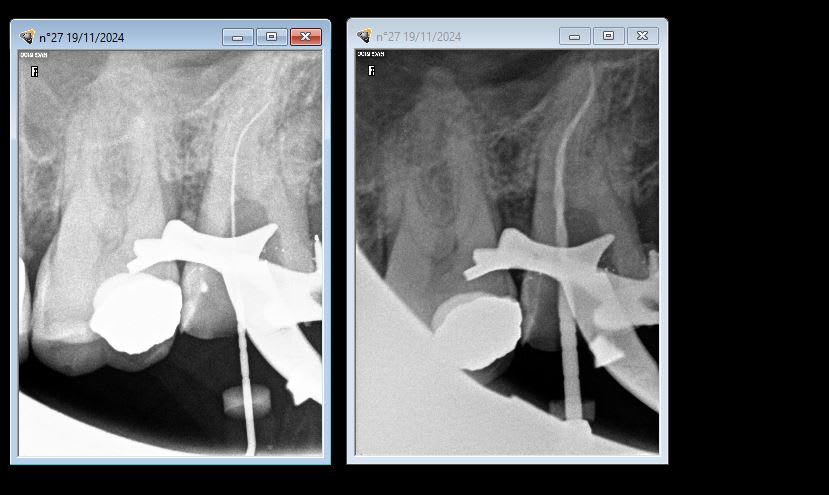

patient pris au hasard toutes les endos que j'ai faites sur ce patient.

> patient pris au hasard toutes les endos que j'ai faites sur ce patient.